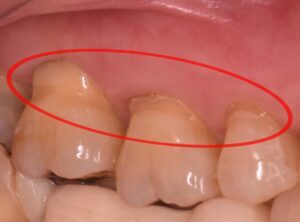

知覚過敏の原因のひとつとして、歯と歯茎の境目付近の歯質が欠けてしまい、神経が近くなることでしみる症状が出ることがあります。この状態が、昔から「くさび状欠損」と呼ばれてきたものです。

NCCLは「虫歯ではなく、歯の一部が失われてしまう状態」の一種で、特に歯のくびれた部分に生じるものと定義されています。最近では「Tooth Wear(歯の摩耗・損耗)」という言葉もよく使われるようになっています。